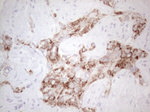

AMACR Antibody in Immunohistochemistry (Paraffin) (IHC (P))

AMACR Antibody (TA808476) in IHC (P)

Immunohistochemical staining of paraffin-embedded human Kidney tissue within the normal limits using anti-AMACR mouse monoclonal antibody. (Heat-induced epitope retrieval by 1mM EDTA in 10mM Tris buffer (pH8.5) at 120°C for 3 min, TA808476)(1:150). {{ $ctrl.currentElement.advancedVerification.fullName }} 验证信息 View more